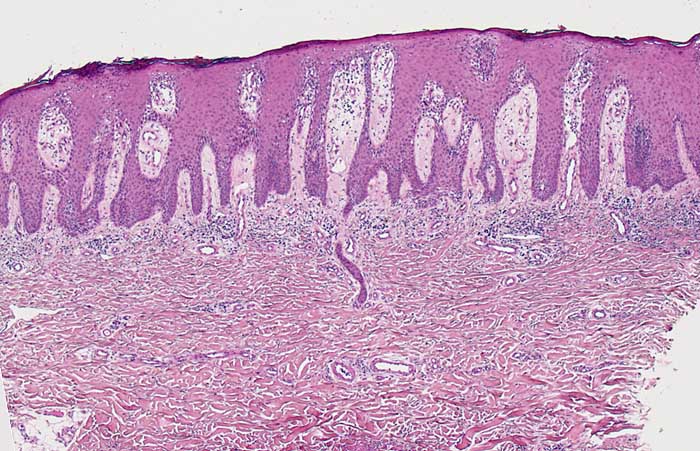

Psoriasis

Die Psoriasis vulgaris als häufigste Form der Psoriasis ist durch die typischen scharf begrenzten, rot-entzündlichen Herde mit silbrig-weißer Schuppung charakterisiert. Je nach Lokalisation und Ausprägung der Veränderungen werden Varianten der Erkrankung unterschieden. Die verschiedenen, eher selten auftretenden Formen der Psoriasis werden anhand Ihres Aussehens unterschieden. Dazu zählt auch die hier abgebildete Psoriasis guttata.

• Hyperparakeratotische Verhornung der Epidermis (verdickte, kernhaltige Hornschicht)

• Ausgedünntes oder fehlendes Stratum granulosum

• Psoriasiforme Epithelhyperplasie: Gleichmässige Akanthose mit verlängerten epidermalen Reteleisten, die zur Basis verbreitert sind und hochgezogene dermale Papillen.

• Munro-Mikroabszesse (Ansammlung neutrophiler Granulozyten in der Hornschicht und subkorneal)

• Verschmälerung der suprapapillären Epidermis

• Dilatierte gewundene Kapillaren im Bereich der papillären Dermis

• Papillenödem

• Oberflächlich perivaskuläres lymphozytäres Entzündungsinfiltrat